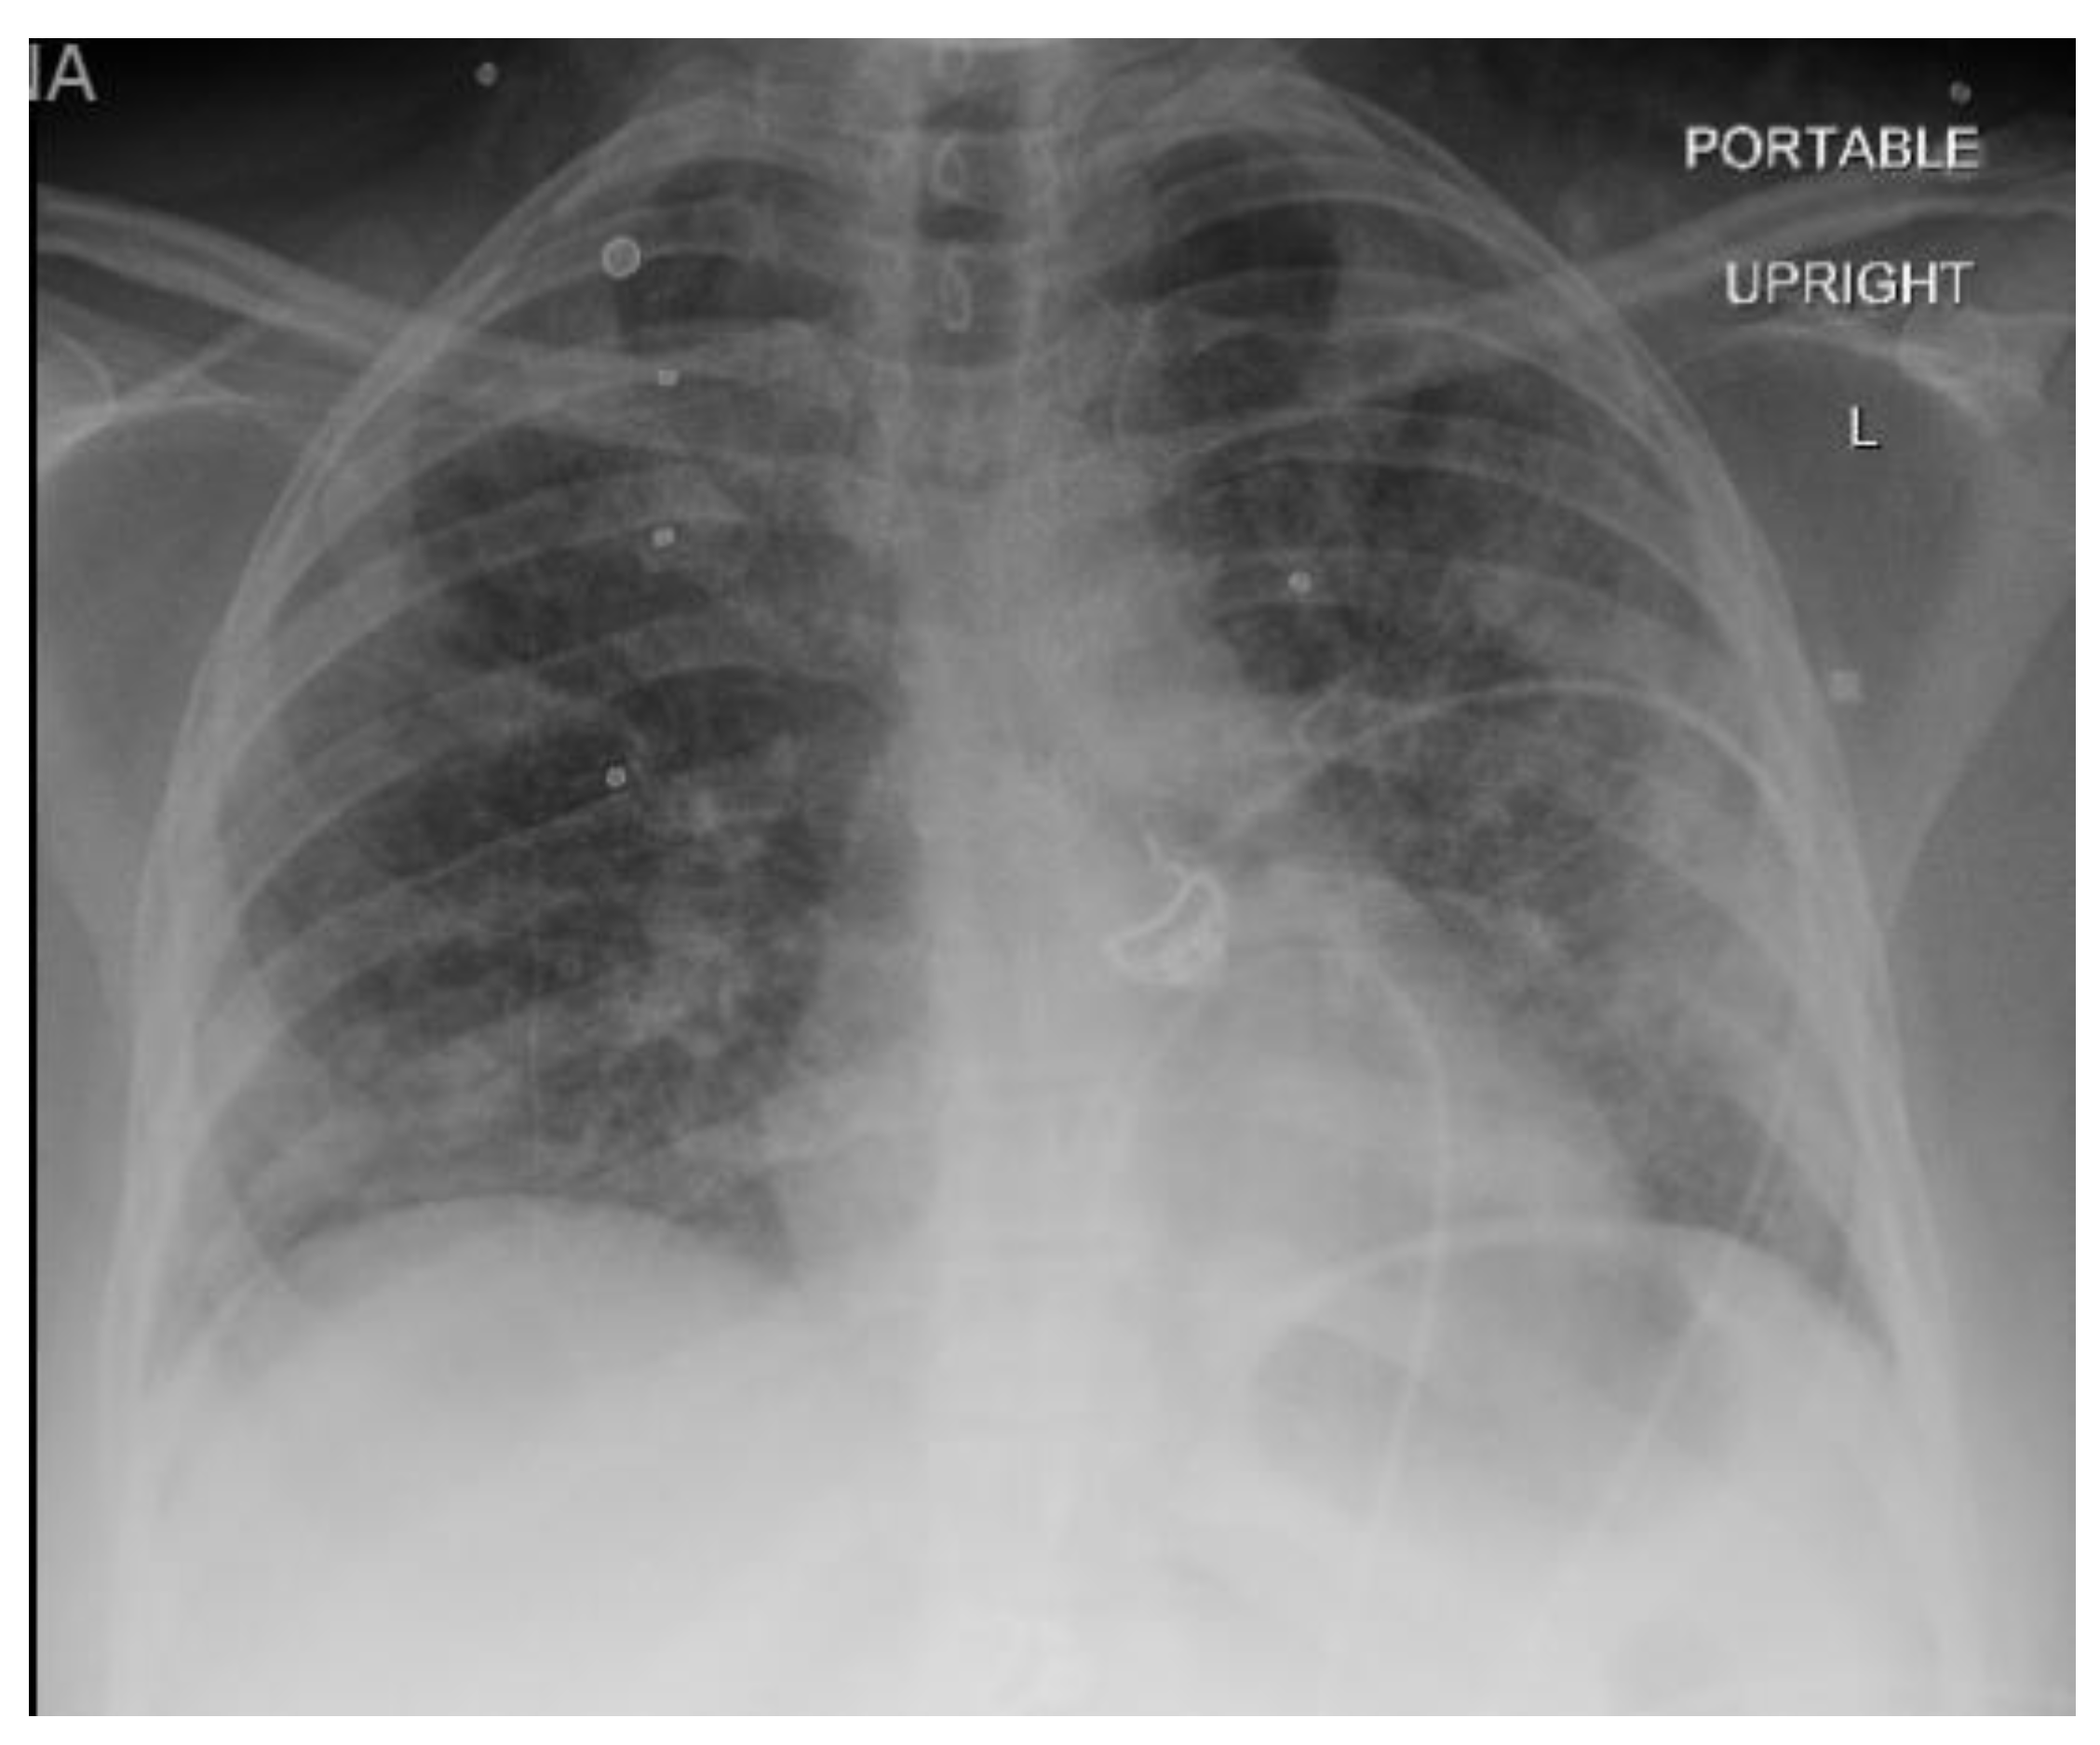

A 40-year-old female with a past medical history of asthma who presented to an outside hospital with a 3-week history of coughing, wheezing, and dyspnea, was found to have extensive bilateral ground glass opacities on CT scan and X-ray of the chest (Figure 1 and Figure 2). Admission testing revealed she was HIV positive with a CD4 count of 9 cells/ml and a viral load of 20,800. Additionally, she tested positive for P. jirovecii via direct immunofluorescence on admission for which she was treated with trimethoprim/sulfamethoxazole (TMP/SMX) and prednisone. Despite ongoing treatment, her clinical status continued to decline necessitating mechanical ventilation 10 days after admission. At this time, she underwent bronchoalveolar lavage which was positive for cytomegalovirus by polymerase chain reaction testing in addition to serum positive CMV (viral load of 175,000), for which ganciclovir was initiated and maintained for 11 days. PCR test of BAL was also positive for CMV, suggesting CMV pneumonia. Unfortunately, she progressed into ARDS refractory to lung-protective ventilation, prone positioning, and inhaled nitric oxide. She was transferred to our facility for evaluation of ECMO therapy at hospital day 18 (8 days after intubation). At the time of transfer, arterial blood gas analysis showed hypoxia (PaO2 of 79 mm Hg) on 100% fraction of inspired oxygen (FiO2), on Bi-level with P high/P low (30/1 cmH2O) and T high/T low (3/0.6 sec). Of note, patient was not able to promptly receive antiretroviral therapy (ART) upon diagnosis of HIV in the setting of ileus due to poor enteral absorption and acute kidney injury. ART with abacavir, lamivudine, and dolutegravir was immediately started on ECMO day 1 when her symptoms of ileus began to resolve.

Figure 2. Chest X-Ray demonstrating extensive patch infiltrates in bilateral lung.